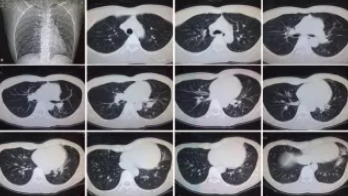

CT检查原理是X光分层穿过人体,这就像把面包切成薄片,每一片都可以摊开看。当遇到外伤怀疑伤到骨头,可以选择CT观察隐匿损伤或软组织损伤。

CT适用于头部、胸部、腹部、盆腔、脊柱、四肢、骨骼等处,由于它的特殊诊断价值,已经广泛应用于临床,特别是在肿瘤的诊断上更是具有很高的应用价值。但由于CT设备较为昂贵,检查费用也会偏高,对于某些部位的检查和诊断价值,尤其是定性诊断,还有一定限度,所以在临床上并没有将CT检查视为常规诊断手段。此外,CT诊断辐射量大于DR,所以怀孕或备孕期女性不宜进行CT检查。